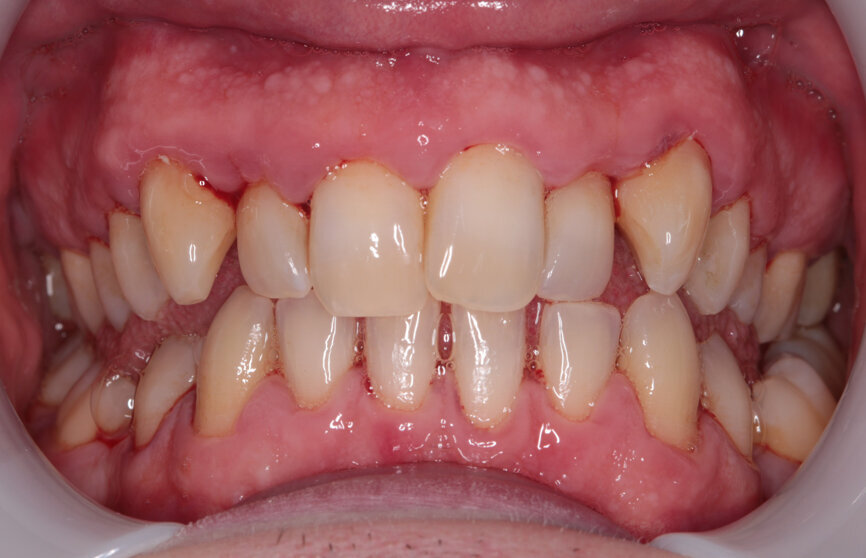

My examination revealed nothing abnormal with his extra- or intra-oral soft tissue, temporomandibular joint or range of motion. However, his oral hygiene was poor, which was not helped by the crowding of his maxillary anterior segment. In addition, tooth #48 was carious. I carried out a full orthodontic assessment (Table 1) and took photographs.

I explained that the maxillary teeth could and should be aligned, as this would likely result in easier cleaning of the teeth, plus it would improve the appearance. The patient and I agreed that the mandibular teeth could remain untouched, as this would keep the cost down, but mainly because they did not bother him. The priority was to stabilise his periodontal condition. A basic periodontal examination Code 3 and heavy bleeding were recorded in each sextant. At that visit, I performed a gross scaling using the ultrasonic scaler and used a model to demonstrate both the use of flossettes and an oscillating toothbrush.

Two weeks later, the colour and contour of the patient’s gingival margins were as healthy as could be considering the crowding of the teeth. We discussed what treatment with ClearSmile Aligners would involve, such as interproximal reduction (IPR), compliance and risks, and a referral for specialist orthodontics was offered. Preferring to proceed with clear aligners, the patient signed off his full consent, and a two-stage putty impression was taken using a separation wafer. The Archwize digital planning software was used to predict tooth movement and necessary IPR throughout treatment. It suggested that 18 maxillary aligners would be needed.

Outcome

While the patient arrived with misaligned teeth that were difficult to clean and gingivae that reflected this, he left with clean, light teeth, pink gingivae and a much straighter smile. He was very pleased and expressed warm gratitude for his treatment. He practised every bit of advice given with conspicuous diligence and as a result he reaped the rewards.

Fig. 7: Post-scaling anterior view